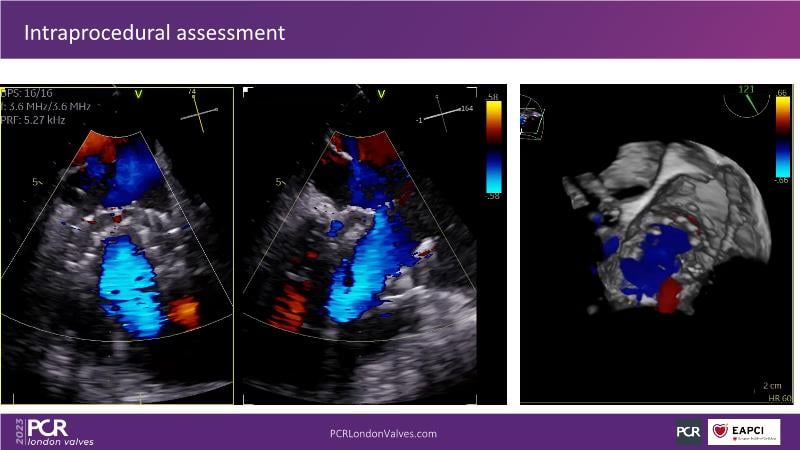

This session explores the features of the PASCAL Precision and the EVOQUE tricuspid replacement systems through simulators and case presentations, while a panel of experts discuss the technology, witnessing live demonstrations of treating mitral and tricuspid regurgitation patients.

- To learn about the differentiating features of the PASCAL Precision system showcased in a series of simulators alongside case presentations

- To interact with a panel of experts discussing the PASCAL Precision system technology and showcasing, live, its different key features in action and how they help treat mitral regurgitation and tricuspid regurgitation patients